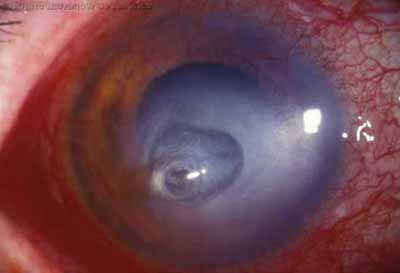

En su evolución se observará aumento del edema, aparición de un anillo inmunológico (Wessely), agrandamiento y coalescencia de los infiltrados que progresan hacia la formación de un absceso, queratolisis superficial, adelgazamiento y perforación corneal.

Anillo inmunológico de Wessely

- Es la expresión de la interacción de los antígenos extraños con los anticuerpos que se difunden desde los vasos limbares hacia el estroma.

- Representa la formación de un complejo inmune que activa el sistema del complemento.

- El anillo de Wessely contiene principalmente neutrófilos

- Puede aparecer en procesos no infecciosos

La vascularización y el hipopion son poco frecuentes en los estadios tempranos de la queratitis. Con el tiempo, en los estados avanzados de invasión estromal, aparecen vasos estromales